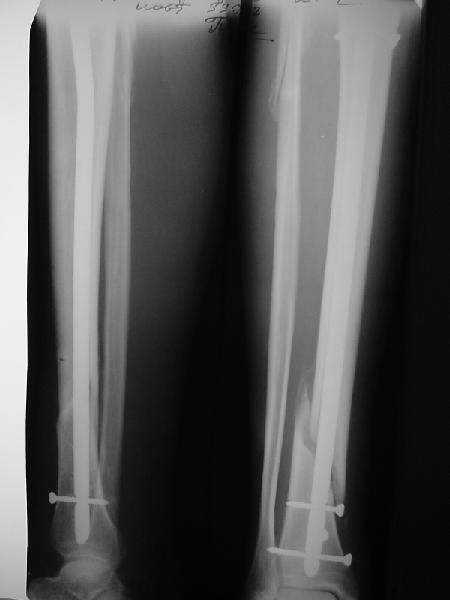

Как мне показать пример? Фото стоящего на одной оперированной конечности пациента? O! Пример, подвигнувший нас на некоторое изменение технологий. Пациент этот ходил с полной нагрузкой вопреки рекомендациям. В качестве подтверждения - сломанный проксимальный статический винт к 1 мес., а к 2 мес. - все остальные. Сейчас мы перешли на более fool-proof остесинтез.

На мой взгляд, на снимках, приведённых Вами - неправильно сростающийся перелом дистальной трети большеберцовой кости, состояние после остеосинтеза интрамедуллярным гвоздём.

Как Вы пишите снимок под номером 1 - менсяц после операции, под номером 2- два месяца после операции.

I think that the X-Rays show S/P IMN of Spiral # of the Distal Tibia consoles in misalignment.

You wrote that a picture number 1 - f month after the surgery, and number 2-two months after the surgery.

Ok. А также и следующий, в 3 месяца.